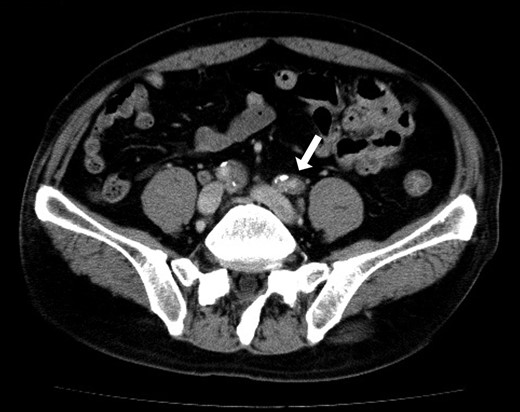

He underwent an elective laparoscopic abdominoperineal resection with a lithotomy position. There was no vascular injury or compression with laparoscopic forceps as far as we were able to recognize retrospectively based on the laparoscopic video and the memory. The duration of surgery was 4 hours and 48 minutes. Blood loss was estimated 100 ml, the urine volume was only 50 ml during the operation. In-out balance during operation divided body weight and time of operation was 6.38 ml/kg/h. The patient reported a severe pain in the left leg, when he woke up post-operatively. The left leg was pale and cold, associating sensory abnormality and motor dysfunction; left pedal and popliteal pulses were absent. A CT scan revealed the contrast interruption of left common iliac artery (CIA) over 11.5 cm and suspected to be due to an arterial thrombosis (Fig. 2). Under the local anesthetic technique, the left femoral artery was exposed and performed thrombectomy with a 5Fr Fogarty catheter. After a new clot was removed, aortography revealed persistent stenosis in left iliac artery. Consequently, a Percutaneous transluminal angioplasty (PTA) with stent (Express LD 8 × 37 mm) was added (Fig. 3) via left femoral artery. Blood perfusion in his left leg improved markedly immediately post PTA. The patient was transferred to the intensive care unit for two days due to the complications with a rhabdomyolysis (creatinine phosphokinase up to 23 598 IU/l). The patient started walking 5 days post-surgery, however, the patient was left with the numbness in his left lower leg. A heparinization had been commenced on the postoperative day 1, then this was switched to the cilostazol prior to the discharge for home. We note that the patient continued reporting the left lower leg numbness even one year past the surgery.

Postoperative 3D-contrast enhanced CT revealed the complete obstruction of left common iliac artery (CIA). The sagittal section through the left iliac artery and the graph of left CIA’s internal diameter showed significant stenosis.